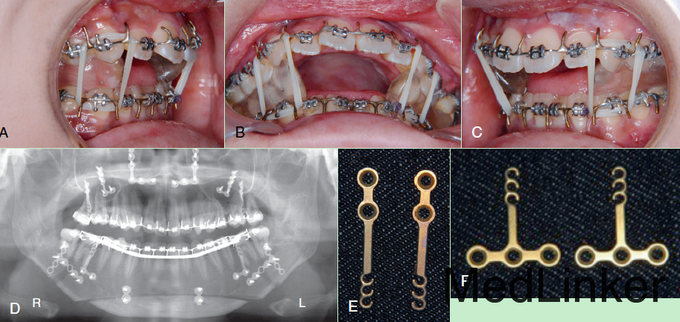

诊断:骨性III类,牙性III类,前牙开合 治疗:正畸-正合联合治疗:Le Fort I 截骨术, 下颌升支矢状劈开(BSSO), 颏部修整术。 但实行Surgery First的做法,先行正合外科治疗,再术后正畸去代偿调整上下牙弓关系。

Surgery First的做法,国内做的比较少,主要原因是直接手术后上下牙弓不协调,有太多的咬合干扰点,不能像传统手术那样用咬合来引导定位手术,正畸科医生和正合外科医生必须要有足够的经验,必须在手术前进行精确的模拟及模型外科设计,否则可出现骨块移动不够,导致术后无法去代偿的情况。本文摘自Nanda《esthetics and biomechanics in orthodontics》